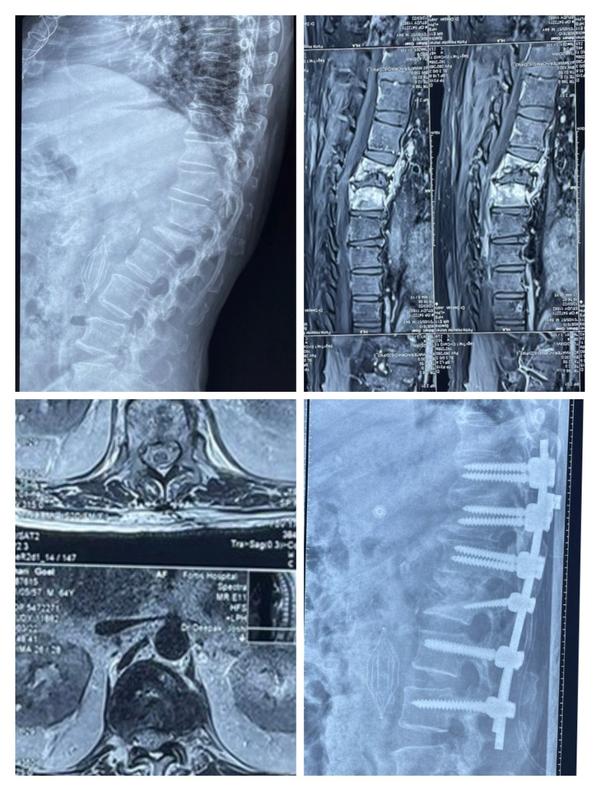

Dr Pramod Saini is an Orthopaedic Spine surgeon with expertise in Minimally Invasive Spine surgery and Endoscopic spine surgery. He is currently working as Senior Consultant with Jaypee hospital, Noida. He is an Orthopaeidic surgeon with special training in spine surgery. He specializes in treating all spine related disorders and his practice is exclusively restricted to Spinal prblems. His area o...